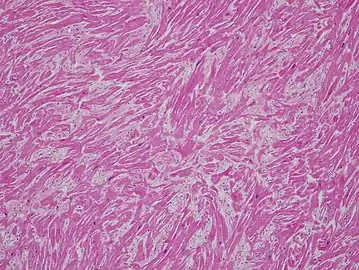

a-c) Histological abnormalities in cardiomyopathy

Stained microscopic section of heart muscle in hypertrophic cardiomyopathy